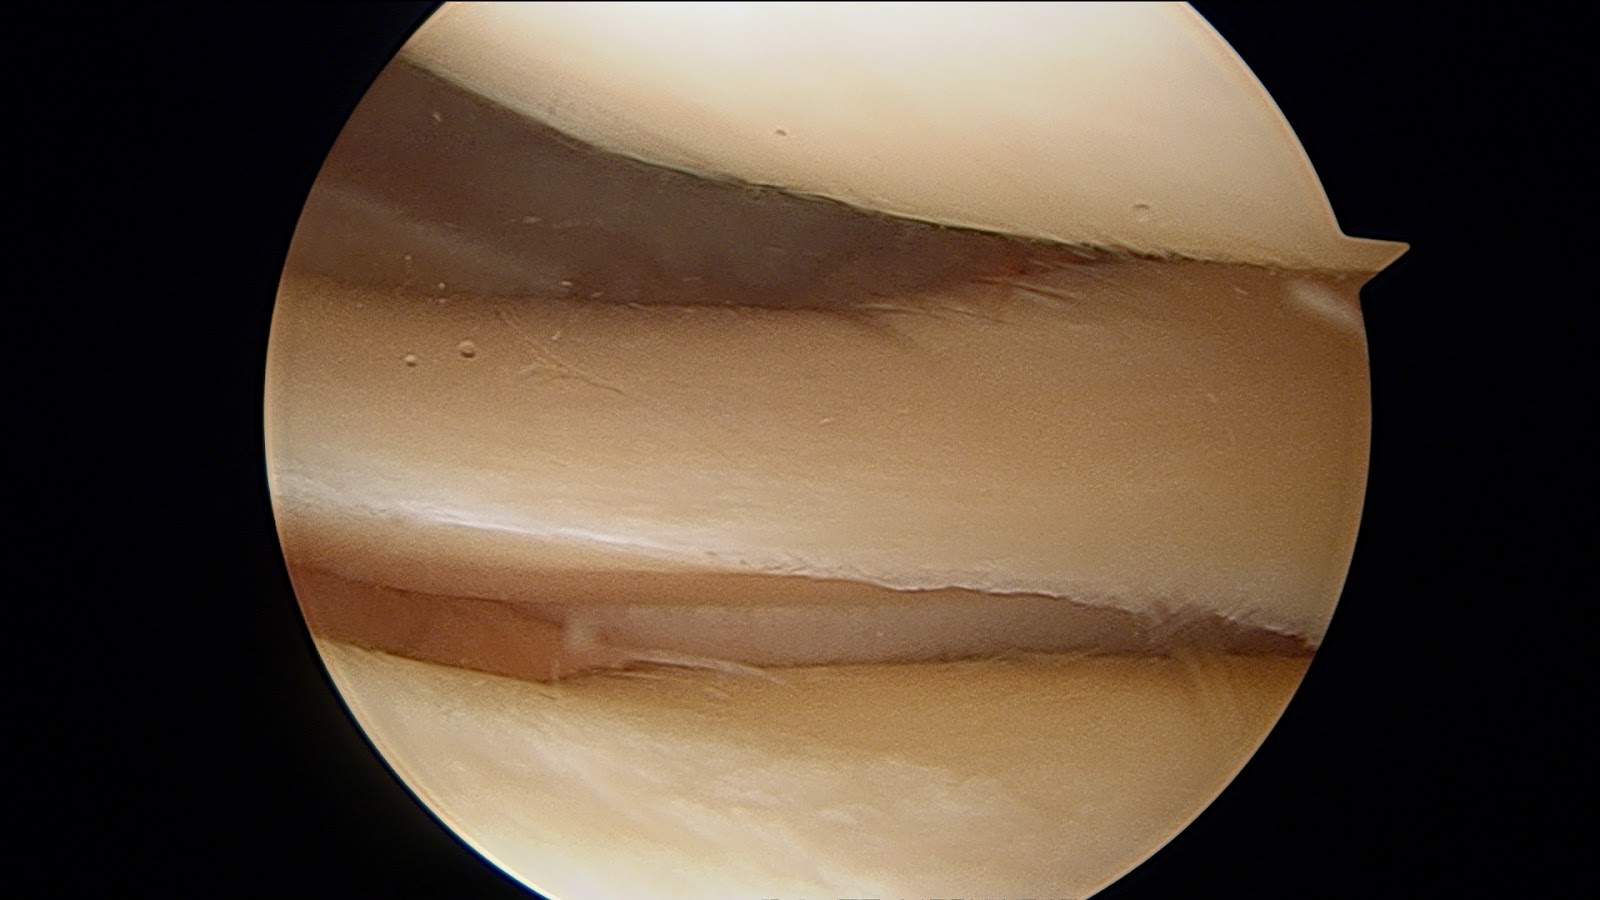

Imagen: se aprecia una ruptura del menisco visto con artroscopia.

Imagen: se aprecia un menisco sano visto con artroscopia.

Imagen: se aprecia un menisco degenerativo (envejecido, deflecado) visto con artroscopia.